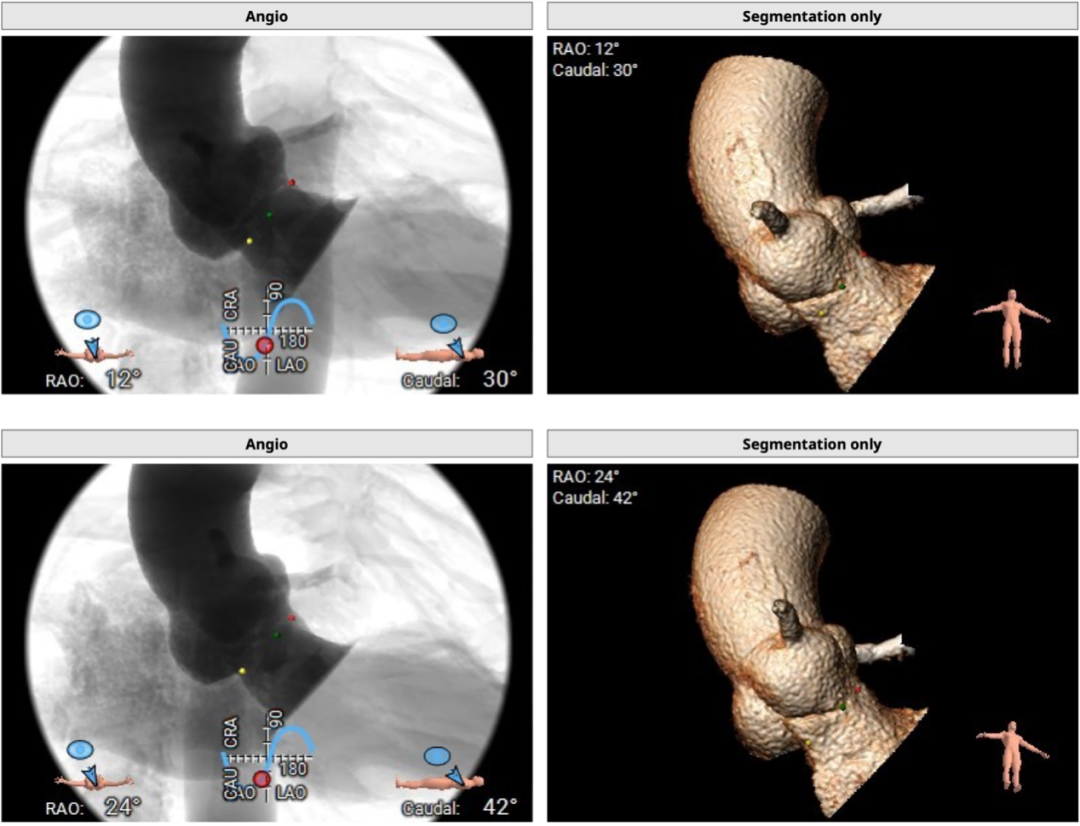

29mm瓣膜模拟效果: